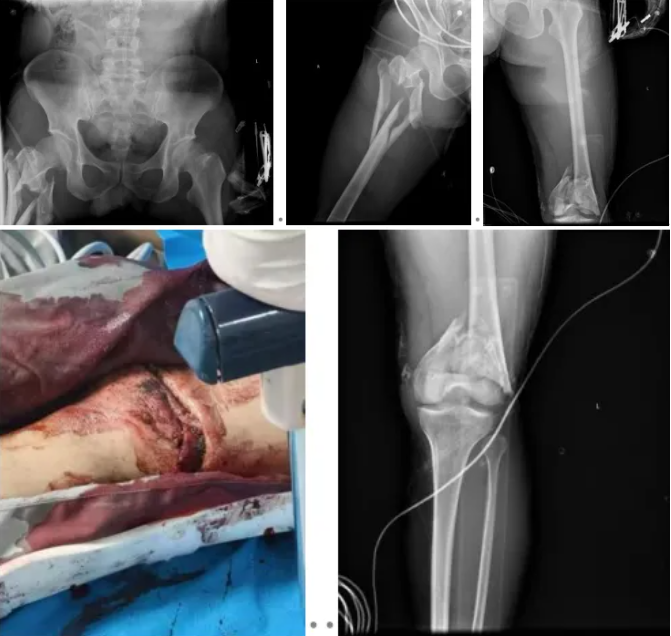

骨科二区薛浩主治医师接诊后查体发现,患者左大腿远端有一长约 15cm 开放性伤口,伴活动性出血且局部污染严重;左前臂、头部等多处有散在皮擦伤,左前臂、腰背部、右大腿近端及右肩疼痛明显、活动受限,末梢血运差,眼睑及甲床苍白。影像学及 CT 检查明确诊断:开放性左股骨远端粉碎性骨折、右股骨近端粉碎性骨折、腰 1 椎体爆裂性骨折等 16 项损伤,其中包括失血性休克、创伤性湿肺、双侧胸腔积液等危及生命的并发症,病情凶险复杂。

患者入院后,骨科二区冉博主任迅速组织团队评估病情,梳理出三大核心治疗难点:一是多发骨折伴大量失血,失血性休克危及生命;二是左膝开放性伤口污染严重,合并多部位骨折需分期手术,创伤大、感染风险极高;三是复合胸部外伤等情况,患者麻醉耐受度差,长期卧床并发症风险高。

“生命至上” 是救治的核心原则。医院立即启动多学科协作机制,骨科牵头联动影像科、重症监护室、心胸血管外科、麻醉手术科等多科室,快速制定个体化分期治疗方案。到院当晚,急诊手术率先开展:对左膝部开放性伤口彻底清创,因骨质缺损多且污染严重,术中创新性使用抗生素骨水泥填充缺损区域,同时以外固定架临时固定左下肢,并行右胫骨骨牵引术。